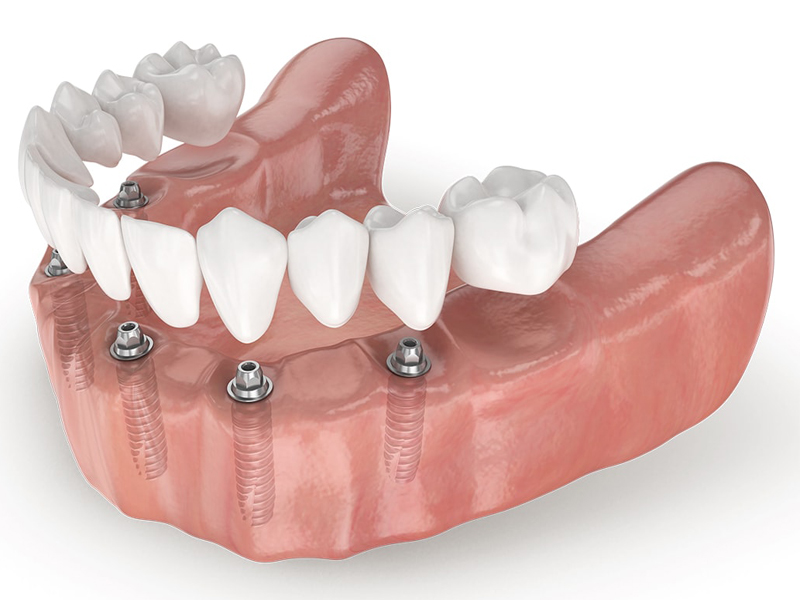

The All on 8 dental implant system consists of positioning 8 dental implants per dental arch, functioning as "anchors" for a fixed and non-removable dental bridge. This system is recommended in cases where the patient has lost more than 80% of his natural teeth.

These dental implants will support a fixed dental bridge (permanently cemented on the implants) between 12 and 14 units (teeth). Before receiving All-on-8, the patient must have enough bone to support the implants. If there is not enough bone, a bone graft is needed. An All-on-8 requires more bone and more bone strength than an All-on-4.

Implant treatment is recommended for patients with a full arch of missing teeth or who are planning to remove and replace the remaining teeth. Offers a stable long-term alternative. If you are diabetic or use tobacco, you may not be the ideal candidate for this procedure.